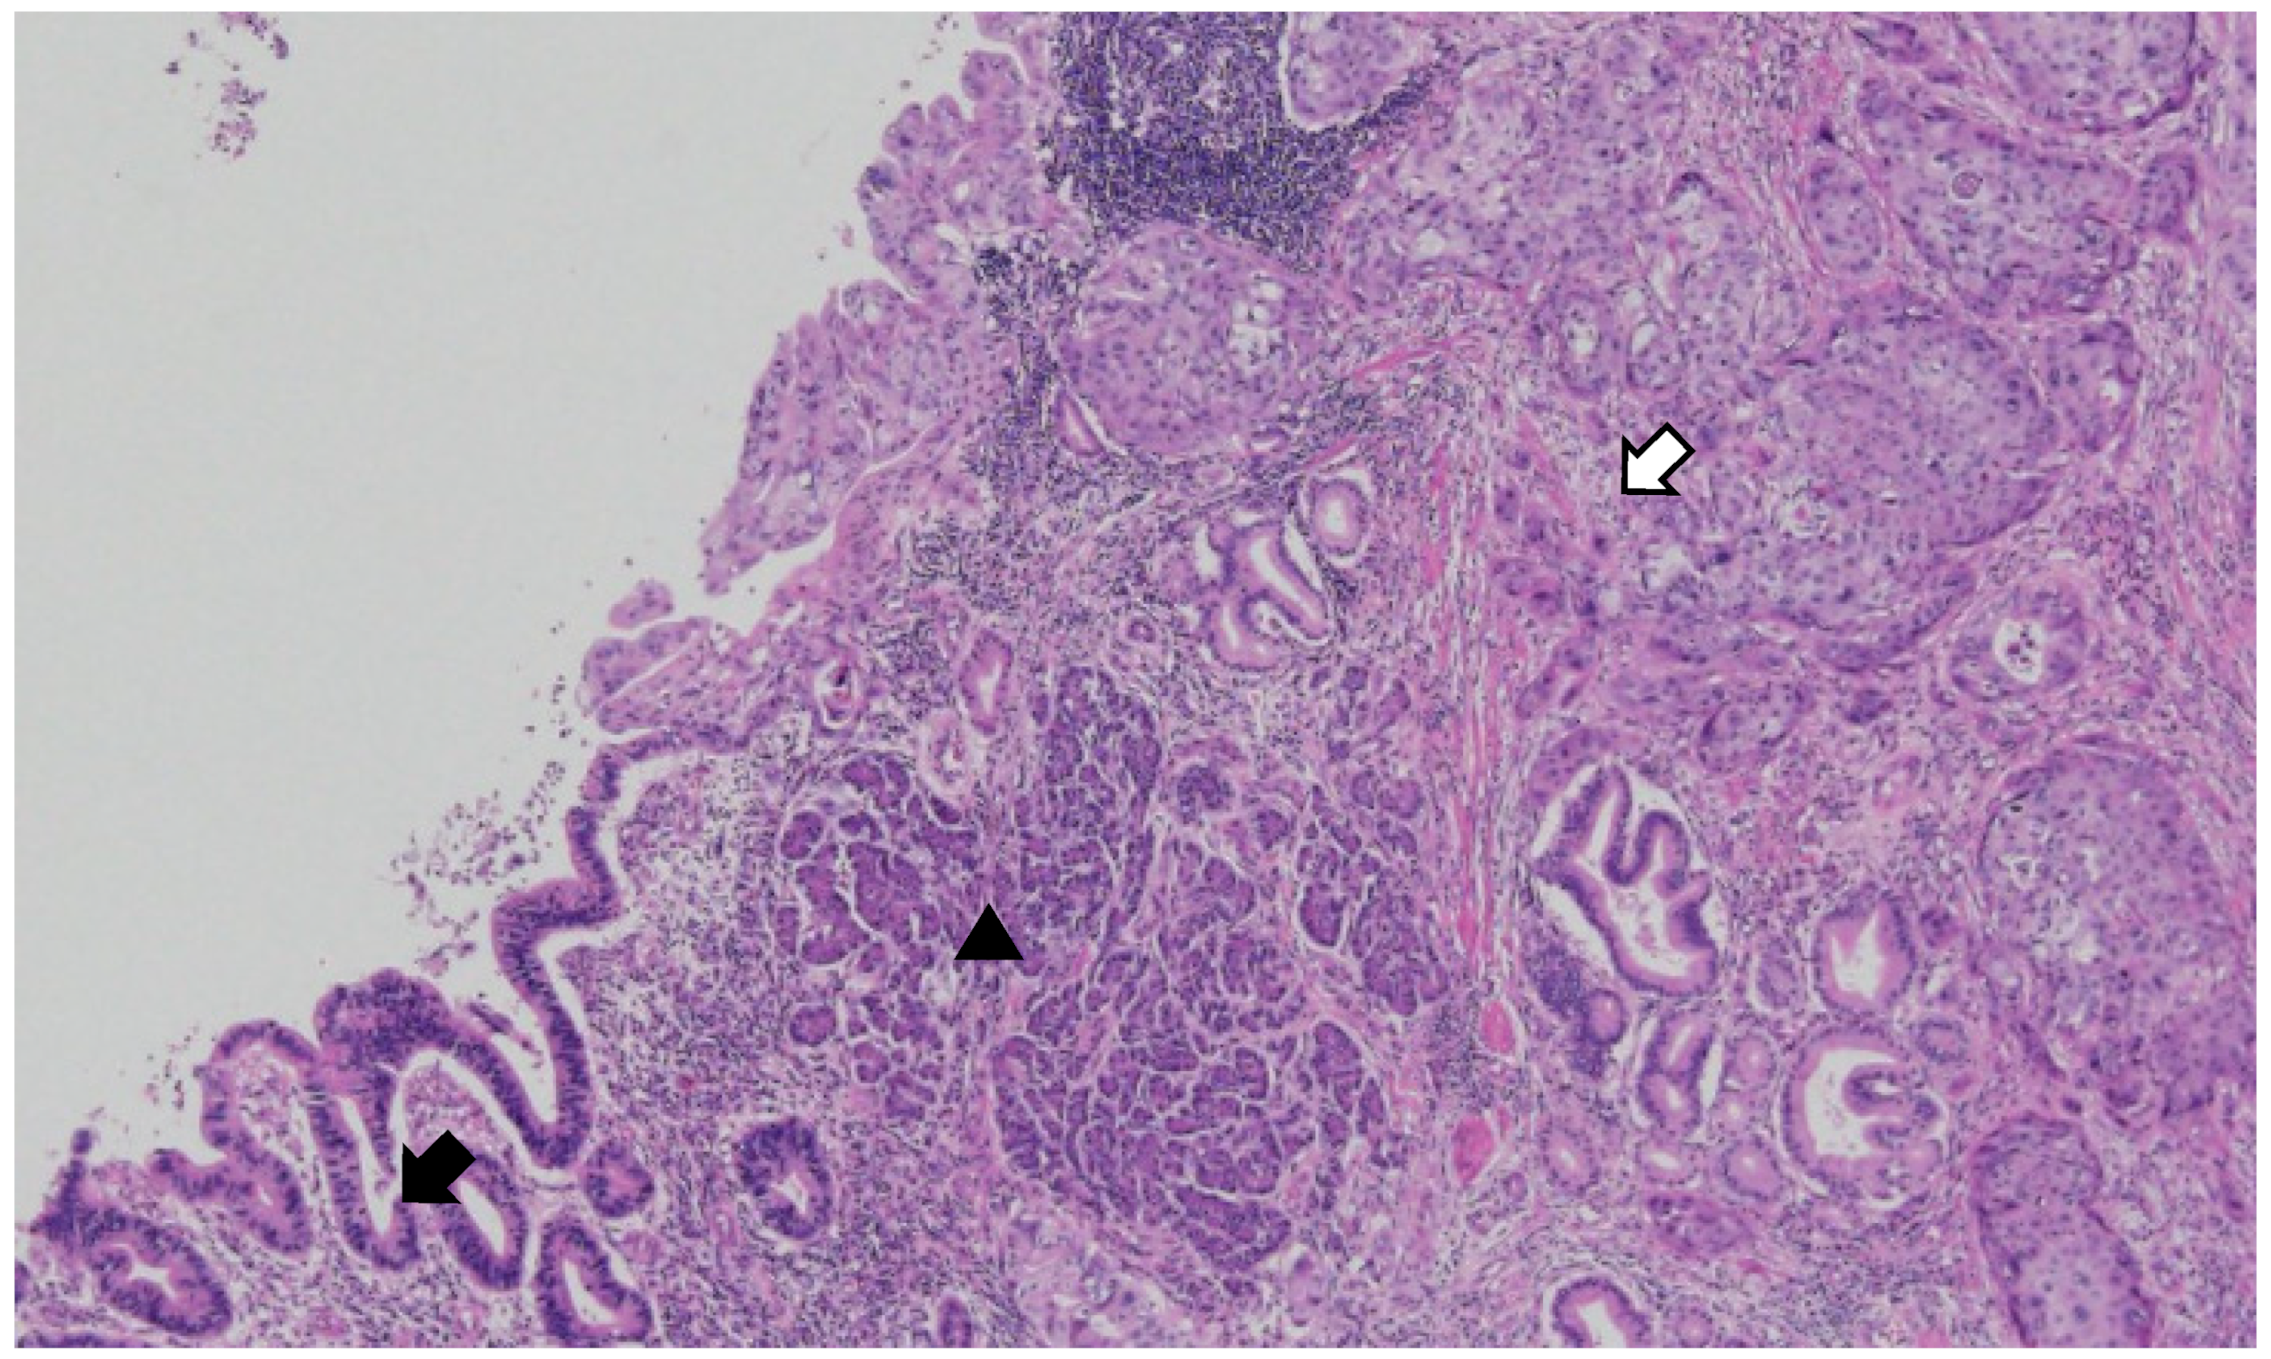

Figure 4.

Mixed adenocarcinoma and squamous cell carcinoma within the duplication cyst. The tumor originates from the ectopic pancreas in the duplication cyst. (Black arrow: adenocarcinoma; white arrow: squamous carcinoma; arrow head: ectopic pancreas) (×40, original magnification). The carcinoma was present in the cystic portion of the proper stomach muscle and had invaded the mucosal layer. Pancreatic tissue was present in the proper muscle layer of the cystic lesion, and the carcinoma originated from the ductal epithelium of the ectopic pancreas. Of the two types of malignant tumors, adenocarcinoma and squamous cell carcinoma, the adenocarcinoma component accounted for approximately 55%, and the squamous cell carcinoma component accounted for approximately 45%. Surgical resection margins tested negative for tumor cells. Lymphovascular and neural invasions were observed. Lymph node (LN) metastasis was observed in 6 of 25 perigastric LNs. In metastatic LNs, the squamous component was predominant.